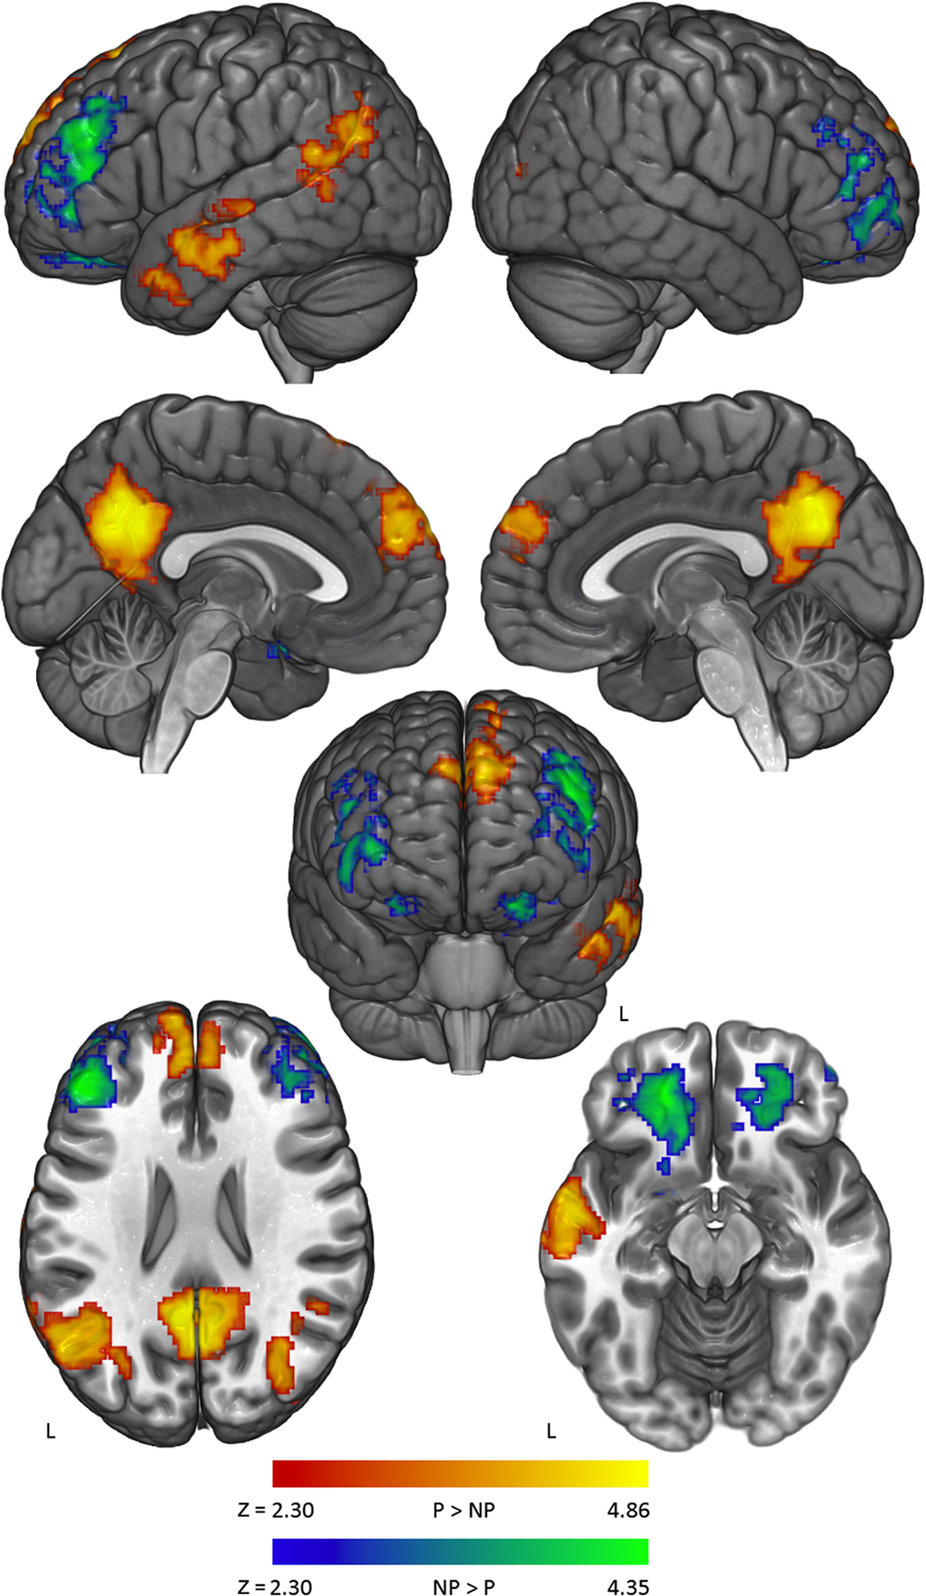

Корреляция активности в некоторых районах при смене убеждений человека. Источник: научная статья "Neural correlates of maintaining one’s political beliefs in the face of counterevidence", Nature, doi: 10.1038/srep39589

На иллюстрациях красным и жёлтым показаны области

Нейробиологи отмечают, что несмотря на индивидуальные особенности каждого человека, отклик на угрозу политическим убеждениям у всех примерно одинаковый. Тем не менее, на примере неполитических убеждений они проверили, как коррелирует активность в некоторых районах

Выяснилось, что у пациентов с большой сопротивляемостью смене убеждений отмечается бóльшая активность в спинной передней части поясной извилины коры головного